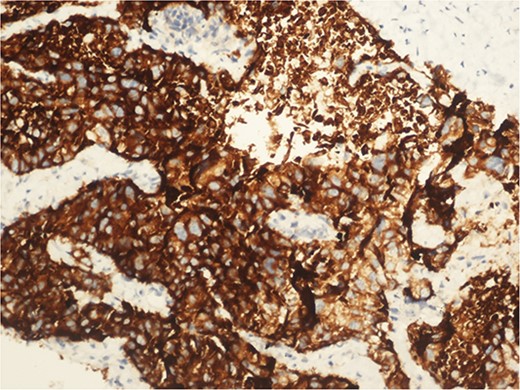

A 59-year-old woman presented with complaints of abdominal pain and abdominal distension for about a month. There was no known systemic disease and no history of previous abdominal surgery. It was learned that the patient had been admitted to the emergency department in another center one month ago with the current complaints and was discharged after medical treatment. Physical examination at the time of admission revealed abdominal distension and diffuse minimal tenderness with no signs of peritoneal irritation. Laboratory tests revealed that hemogram and biochemical parameters were within normal limits, but one of the tumor markers, the patient’s CA 19-9 level was significantly elevated at 855 U/ml (normal range: 0–37 U/ml). Contrast-enhanced CT scan showed a 10×10 cm heterogeneous mass in liver segments 4B-5, extending to segment 6, and free fluid adjacent to the liver and irregular liver contours. Borders of the gallbladder could not be seen. Soft tissues forming nodular mass formation were detected on the omental surfaces (Fig. 1). Computed tomography examination performed at the center where the patient was admitted as an emergency one month ago revealed hypodense lesions measuring 10×8 cm in size in the left lobe of the liver, protruding into the inferior perihepatic area, and 3.5 cm in diameter in segment 5 of the right lobe with no significant contrast enhancement after intravenous injection of contrast material. Perihepatic ascites was not detected and gallbladder size, wall thickness and lumen were normal (Fig. 2). In the light of the radiologic findings, a pre-diagnosis of progressive gallbladder malignancy was considered. The patient was hospitalized in the General Surgery ward for further investigation and treatment. Because of the presence of ascites causing abdominal distension, a percutaneous ascites drainage catheter was placed and 5000 cc ascites drainage was performed. Cytologic examination of the ascitic fluid revealed cell groups with unclear three-dimensional cytonuclear detail among lymphocytes and mesothelial cells with reactive atypia and malignancy was considered suspicious. With the current radiologic and cytologic findings, inoperable metastatic gallbladder carcinoma was considered. Medical treatment was decided by the multidisciplinary oncology council and 18G needle tru-cut biopsy was performed from the 10×10 cm mass adjacent to the gallbladder for definitive tissue diagnosis and adjuvant treatment planning. Histopathologic examination revealed a diagnosis of neuroendocrine carcinoma (NEC) (Fig. 3). Immunohistochemical examination revealed strong staining of tumor cells with CD56 (Fig. 4), synaptophysin (Fig. 5), chromogranin A (Fig. 6), and Ki67 index was >90% (Fig. 7). Weak staining was observed with CK19, CK7, and CDx2, but no staining was observed with CEA and CK20. Morphologic findings were compatible with small cell type. Etoposide and cisplatin chemotherapy was planned but the patient’s general condition deteriorated progressively. The patient couldn’t start chemotherapy and unfortunately resulted in mortality on the 20th day of hospitalization.

The diagnosis of small cell NEC typically involves a combination of clinical evaluation, imaging studies, and histopathological examination. Immunohistochemical staining is crucial for confirming neuroendocrine differentiation, with common markers including synaptophysin, chromogranin A, and CD56. A high Ki-67 index is indicative of the aggressive nature of small cell NEC [2].